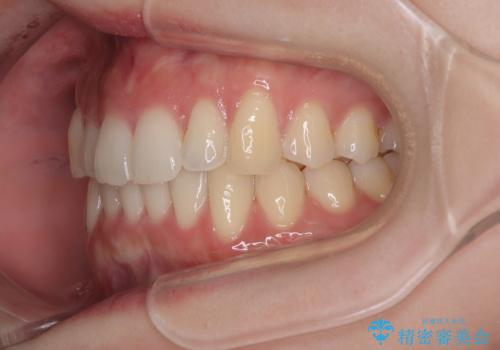

前歯が隠れるほどのデコボコをインビザライン矯正できれいに整える

- 前歯のデコボコを気にして来院された患者様です。

全体的にデコボコが多く、特に下の前歯は隠れてしまうほどの状態でした。

左右ともに奥歯の咬み合わせが理想的な位置にあったこともあり、患者様のご希望通り、インビザラインにて矯正治療を行うこととしました。

マウスピース矯正特有の、奥歯が噛みにくくなるという現象の解消に少し期間をいただきましたが、日々の装着時間を遵守していただき、綺麗な歯列に整えることができました。